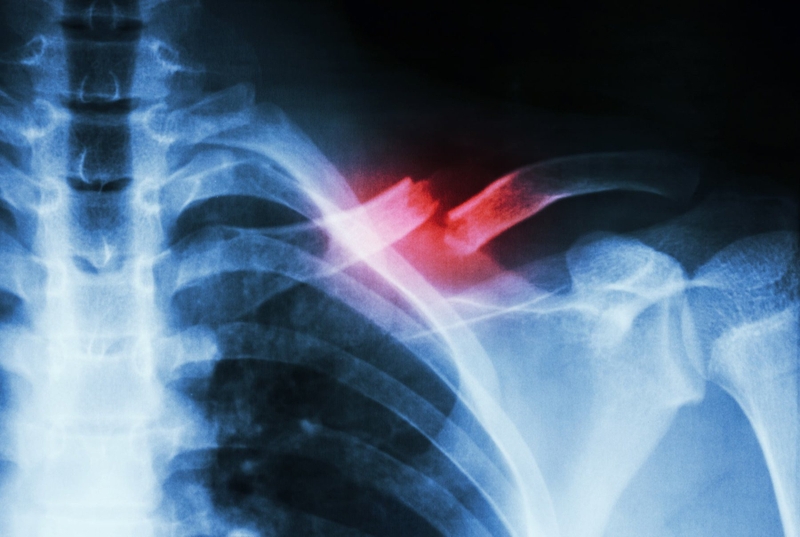

Xương quai xanh có thể bị tổn thương do nhiều nguyên nhân khác nhau, và việc gãy xương quai xanh là một tình trạng phổ biến. Do vị trí nằm dưới da và rất dễ nhận biết, bất kỳ biến dạng hoặc thay đổi nào trong xương này đều có thể dễ dàng nhận thấy.

Mức độ tổn thương của gãy xương quai xanh có thể từ nhẹ đến nặng, bao gồm cả nứt nhẹ, gãy vỡ hoặc gãy thành nhiều đoạn. Xương có thể gãy ở vị trí ban đầu hoặc di chuyển sang vùng lân cận.

Nguyên nhân chính của gãy xương quai xanh thường là do vùng vai chịu tổn thương trong các tình huống như té ngã, tai nạn giao thông, tác động từ vật nặng hoặc tác động mạnh vào khu vực này. Cũng có những trường hợp ở trẻ sơ sinh gặp phải gãy xương quai xanh do rủi ro trong quá trình sinh.

Bệnh nhân cần tuân thủ lịch tái khám định kỳ để đảm bảo xác định liệu vết gãy đã lành hoàn toàn hay chưa. Chụp X-quang là phương pháp kiểm tra cần thiết sẽ được thực hiện trong các lần tái khám để theo dõi tình trạng bệnh.